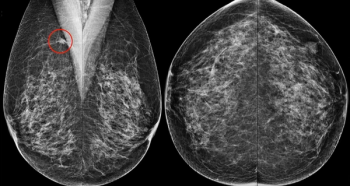

In the third part of a three-part interview from the recent RSNA conference, Mark Traill, M.D., discusses the potential of image-based risk assessment artificial intelligence (AI) algorithms in bolstering adherence to screening protocols for women at high risk for breast cancer.